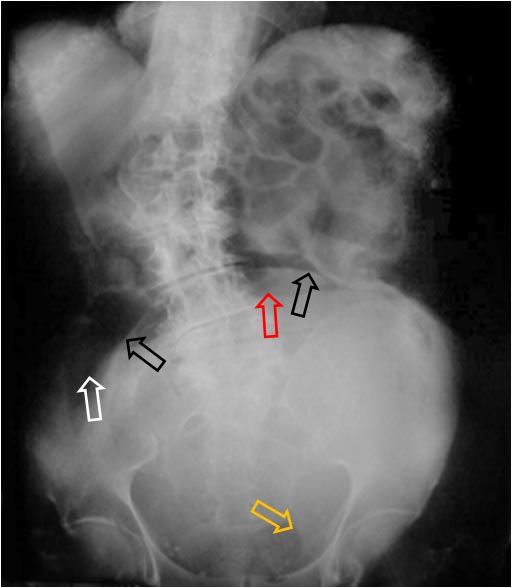

Variante de la normalidad visible hasta en un 10 % de niños, en la urografía intravenosa. Consiste en la presencia de prolongaciones laterales de la vejiga (flechas negras), que desaparecen con la distensión vesical. Corresponden a la herniación extraperitoneal, normalmente bilateral, de la vejiga que ocurre en niños menores de un año y que después normalmente desaparece.

En este caso se trata de un varón adulto en el que persisten estas prolongaciones.

El paciente también tiene calcificaciones prostáticas (flecha roja).